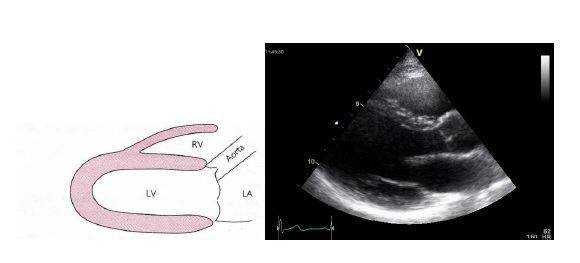

Video 1: echocardiografie parasternale lange as opname (PLAX)

Een lange as opname laat een excentrische sluitlijn zien van de klep en een bolle “opgeblazen” configuratie van de kleppen tijdens systole (doming van de klepblaadjes).

Figuur 1: Hier zie je hoe de klep wat opbolt